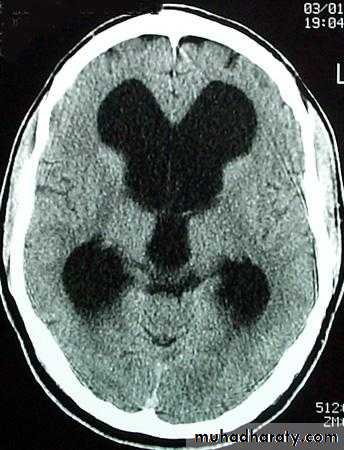

Hydrocephalous

2 typesObstructive ( non – communicating )

Non –obstructive ( communicating )

No obstruction of the ventricular pathway , but the absorption of the csf at the level of arachnoids' granulation is occluded secondary to lodge by blood clot or inflammatory cell or infection post meningitis most commonly to occur post SAH .